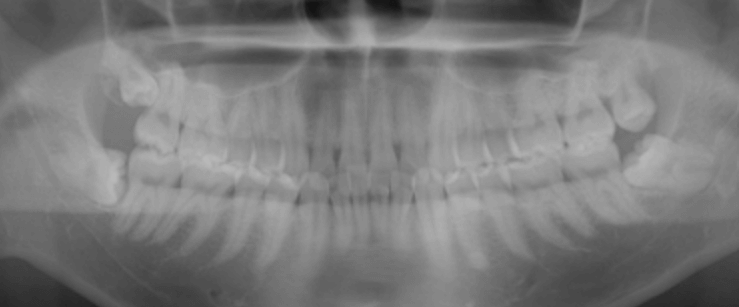

엑스레이 사진을 보시면 치아 아래 부분으로 신경이 지나가는데 이 신경이 발치하려는 치아랑 인접해 있으면 발치가 어렵대요. 저는 2D촬영 말고 3D 촬영으로 찍어야 정확한 신경과 치아의 거리를 알수 있어서 찍고 발치가 가능하다는 판정을 받았어요.